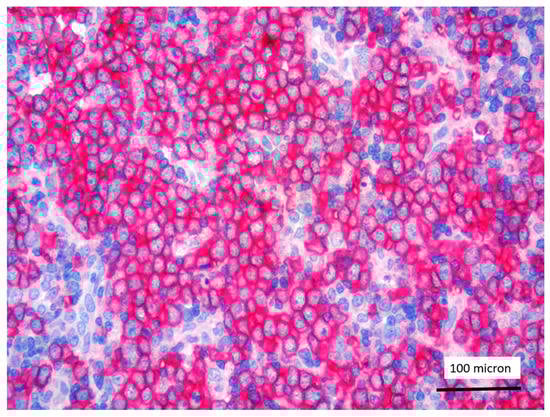

In all the cases, the lymph node histology and immunohistochemical profile were consistent with T-LBL diagnosis. The nodal architecture was effaced by a diffuse proliferation of medium-sized cells with dispersed chromatin and scarce cytoplasm (Figure 1) with high proliferative fraction and usually positive for TdT (Figure 2), CD1a and T-cell markers such as CD3 (Figure 3), CD2, CD8, CD5, CD7. B-cell markers (CD79α, CD20, PAX5 and CD22) were mostly negative; a weak CD79α co-expression was noted in 2/11 cases; myeloid (MPO, CD117, CD68KP1) and monocytic (CD68PGM1) markers were negative. In 5/11 cases, a minor component of immature myeloid cells was identified (Figure 4). Aggregates of mature eosinophils (Figure 5) admixed to the lymphoblastic proliferation were noted in 5/11 cases, whereas clusters of proerytroblasts (Figure 6 and Figure 7) were identified within T-LBL in 1/11 cases. Unexpectedly, LMO2 immunostaining was found to be negative in 9/11 T-LBLs (Figure 8); in the remaining 2 cases, LMO2 was partially expressed (less than 30% of cells) with either moderate or low degree of intensity, respectively (Figure 9).

T-LBL almost universally overexpress LMO2 [14,15]. Unexpectedly, in our series, the majority of T-LBL occurring in the context of M/LNs-Eo was LMO2 negative, with only 2 cases showing partial LMO2 expression with moderate and low degree of intensity, respectively. Jevremovic et al. reported that LMO2 represents a marker commonly expressed by T-LBL and absent in thymocytes of normal thymus and thymomas [15]. Since there is no specific immunophenotypic profile to distinguish thymocytes or thymic epithelial tumors from neoplastic T lymphoblasts, LMO2 is currently considered a useful marker in discriminating thymoma from T-LBL, being almost universally expressed in T-LBL [15]. Recently Brar et al. identified LMO2 as a sensitive and specific marker for differentiating T-LBL from iT-LBP, which were found to be LMO2-negative [16]. The absence of LMO2 expression in iT-LBP was considered by Brar et al. consistent with a thymic origin for iT-LBP as T-lymphoblasts in the thymus do not express LMO2 [16].

Figure 9. Partial and weak LMO2 expression of T-LBL (case 2, immunostaining, magnification 400×).